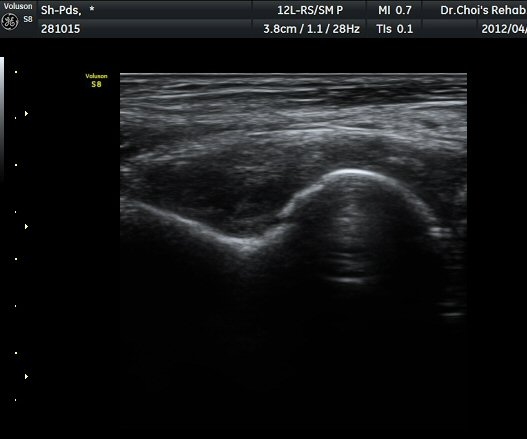

ÃÊÀ½ÆÄ °Ë»ç

ÆÈ²ÞÄ¡°üÀý ¾ÕÀÇ Á¾´Ü¸é°Ë»ç¿Í ÁÖµÎ¿Í Á¾´Ü¸é°Ë»ç¿¡¼­ ½ÉÇÑ °üÀý³» ºÎÁ¾ÀÌ

°üÂûµÊ(»çÁø 1, 2, 3).